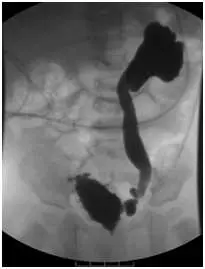

從提供的兩張 VCUG 影像可見:

- 排尿相側位影像顯示遠端前列腺部尿道明顯擴張(an elongated, dilated posterior urethra),典型「windsock」樣外觀,與正常尿道管徑明顯不同。

上述改變符合 PUV 導致的阻塞後壓力過高,使膀胱壁肥厚形成trabeculae及憩室,同時後段尿道於排尿期因瓣膜阻塞而擴張(obgynkey.com)。